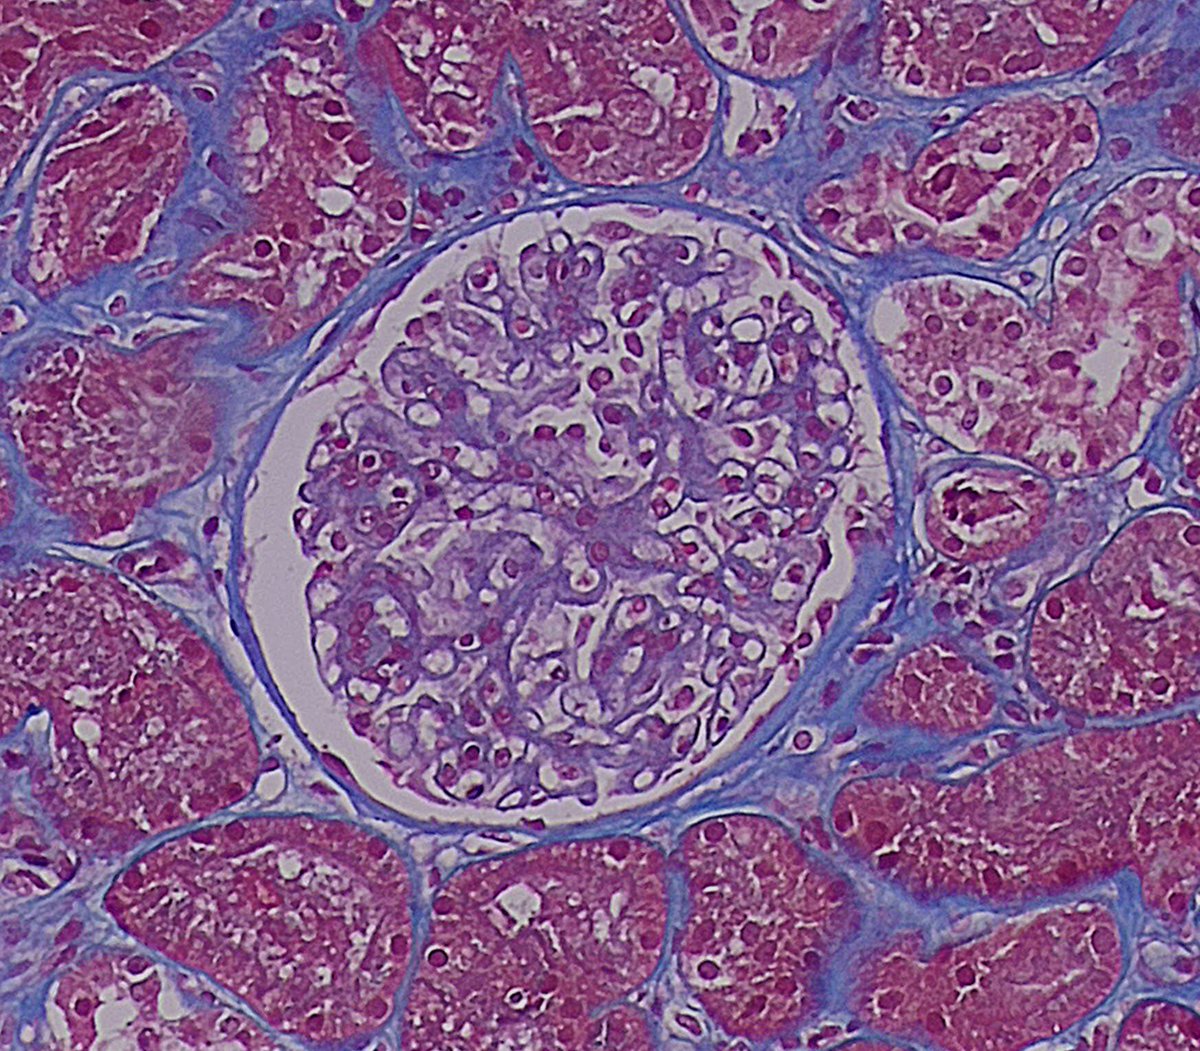

Mujer 👩 47 años Con App: Fibromialgia ????? Debuta con HTA hace 2 meses Proteinuria 24h : 2083.0 mg Ana: positivo Resto inmunológico : negativo Biopsia Renal :

8

9

52

Vamos a hacer una Biopsia ! Y de repente ! Que es esooooooooo?